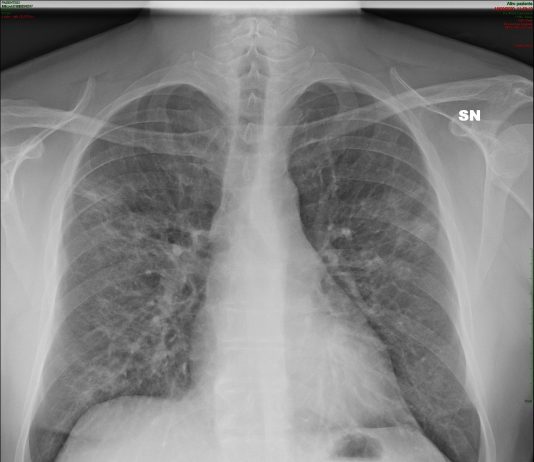

Femmina, 58 anni, asintomatica e apiretica.Esegue come paziente ambulatoriale esterna TC total body per controllo oncologico in neoplasia mammaria, sottoposta nel 2006 a mastectomia con linfoadenectomia, trattata con CT neoadiuvante e RT.